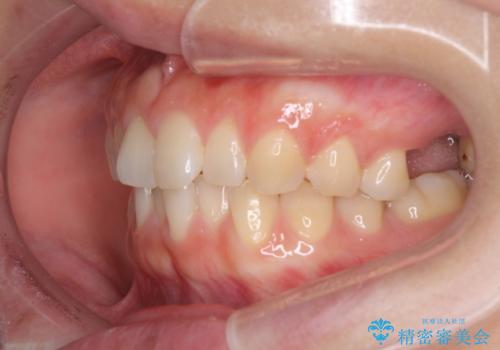

インプラントによる補綴治療とインビザライン矯正

- 抜歯が必要と診断された奥歯を気にして来院された患者様です。

抜歯の上インプラントによる補綴治療を行うこととなりましたが、前歯の叢生も気になるとのことで並行して矯正治療を行うこととしました。

歯列不正は軽微であったので、インビザラインによる矯正治療とし、矯正治療中にインプラント埋入を行う予定としました。

痛みがないので、ボロボロのまま放置していましたが、抜歯後は汚れが溜まりにくくなりスッキリとしたようです。

前歯のデコボコも解消され、ブラッシングが楽になりました。